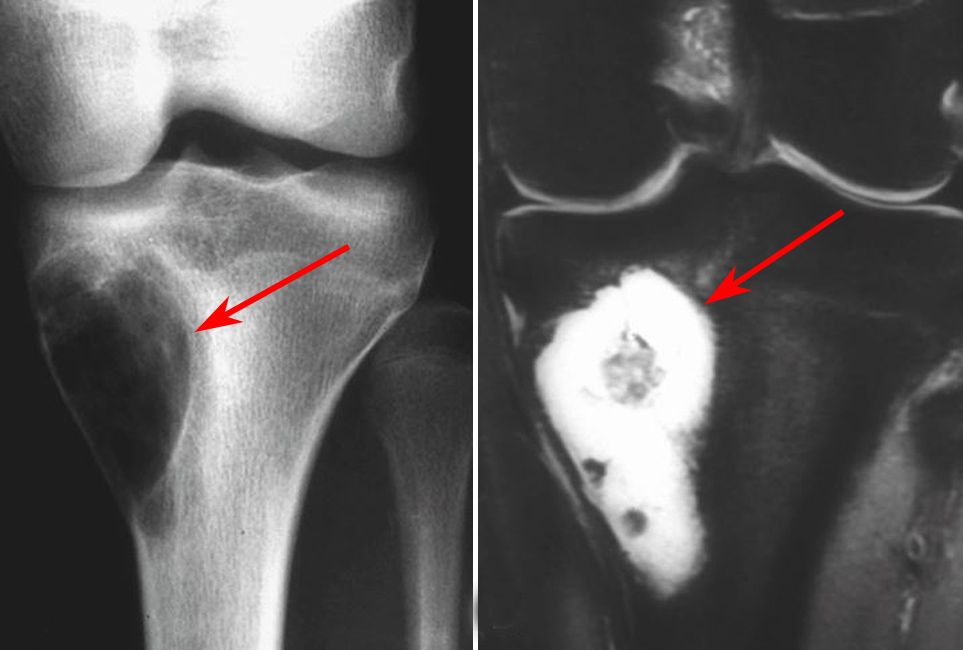

Osteosarcoma Knee - Periosteal Reaction

Osteosarcoma-MRI - Sumer's Radiology Blog

Osteosarcoma Knee - Periosteal Reaction. Imaging characteristics of primary osteosarcoma: Imaging characteristics of primary osteosarcoma: Osteosarcoma is a bone tumor and can occur in any bone, usually in the extremities of long bones near metaphyseal growth plates. Specifically, it is an aggressive malignant neoplasm that arises from primitive transformed cells of mesenchymal origin (and thus a sarcoma). Usually located around the knee in diaphysis or meta/diaphysis and does not occur in hands, feet, spine and flat bones. Children treated with radiation for another cancer also. Osteosarcoma is the most common type of bone cancer, and accounts for about 3% of boys are more likely to have osteosarcoma than girls, and most cases of osteosarcoma involve the knee. Osteosarcoma can cause knee pain or pain and swelling in the affected area. Approximately 800 new cases of. Osteosarcoma is the most common malignant bone tumor.